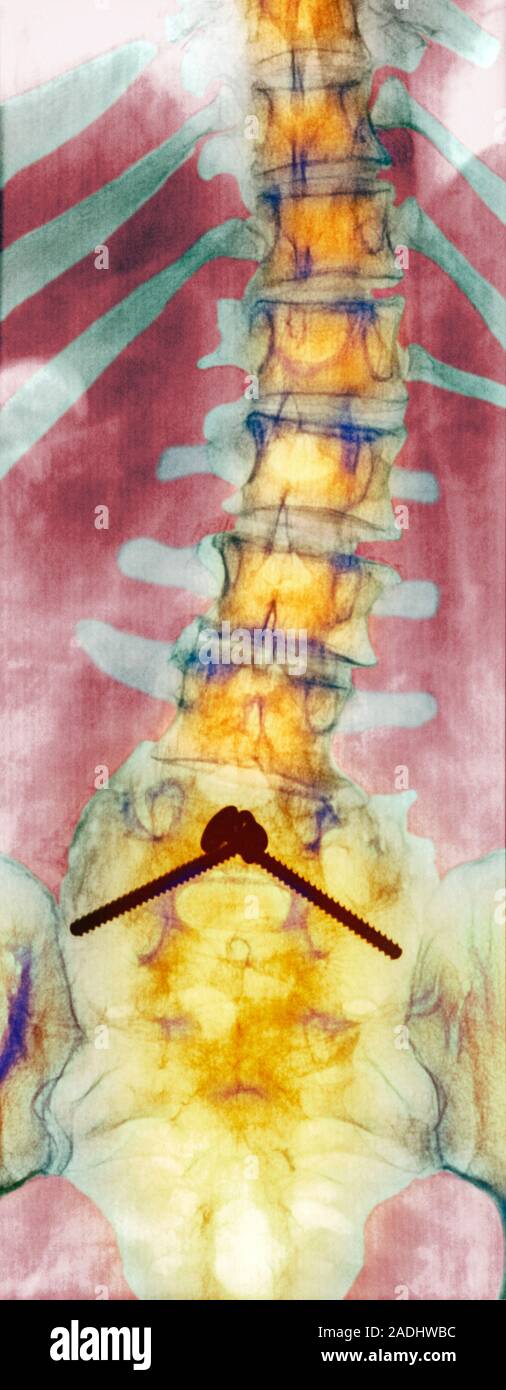

From www.alamy.com

Pinned curved spine. Coloured Xray of bones of the spine and pelvis of Curved Spine Old Age scoliosis is where the spine twists and curves to the side. Kyphosis can also develop as a result of a spinal injury. It can also be the result of abnormal shaped vertebrae or. It can affect people of any age, from babies to adults, but most often starts in. whether you've developed the condition in childhood or as. Curved Spine Old Age.

Pinned curved spine. Coloured Xray of bones of the spine and pelvis of Curved Spine Old Age The risk of hyperkyphosis increases with age, and it is more common. kyphosis is often caused by poor posture during childhood. whether you've developed the condition in childhood or as an adult, the aging process can cause or intensify symptoms of scoliosis or. scoliosis is where the spine twists and curves to the side. It can also. Curved Spine Old Age.